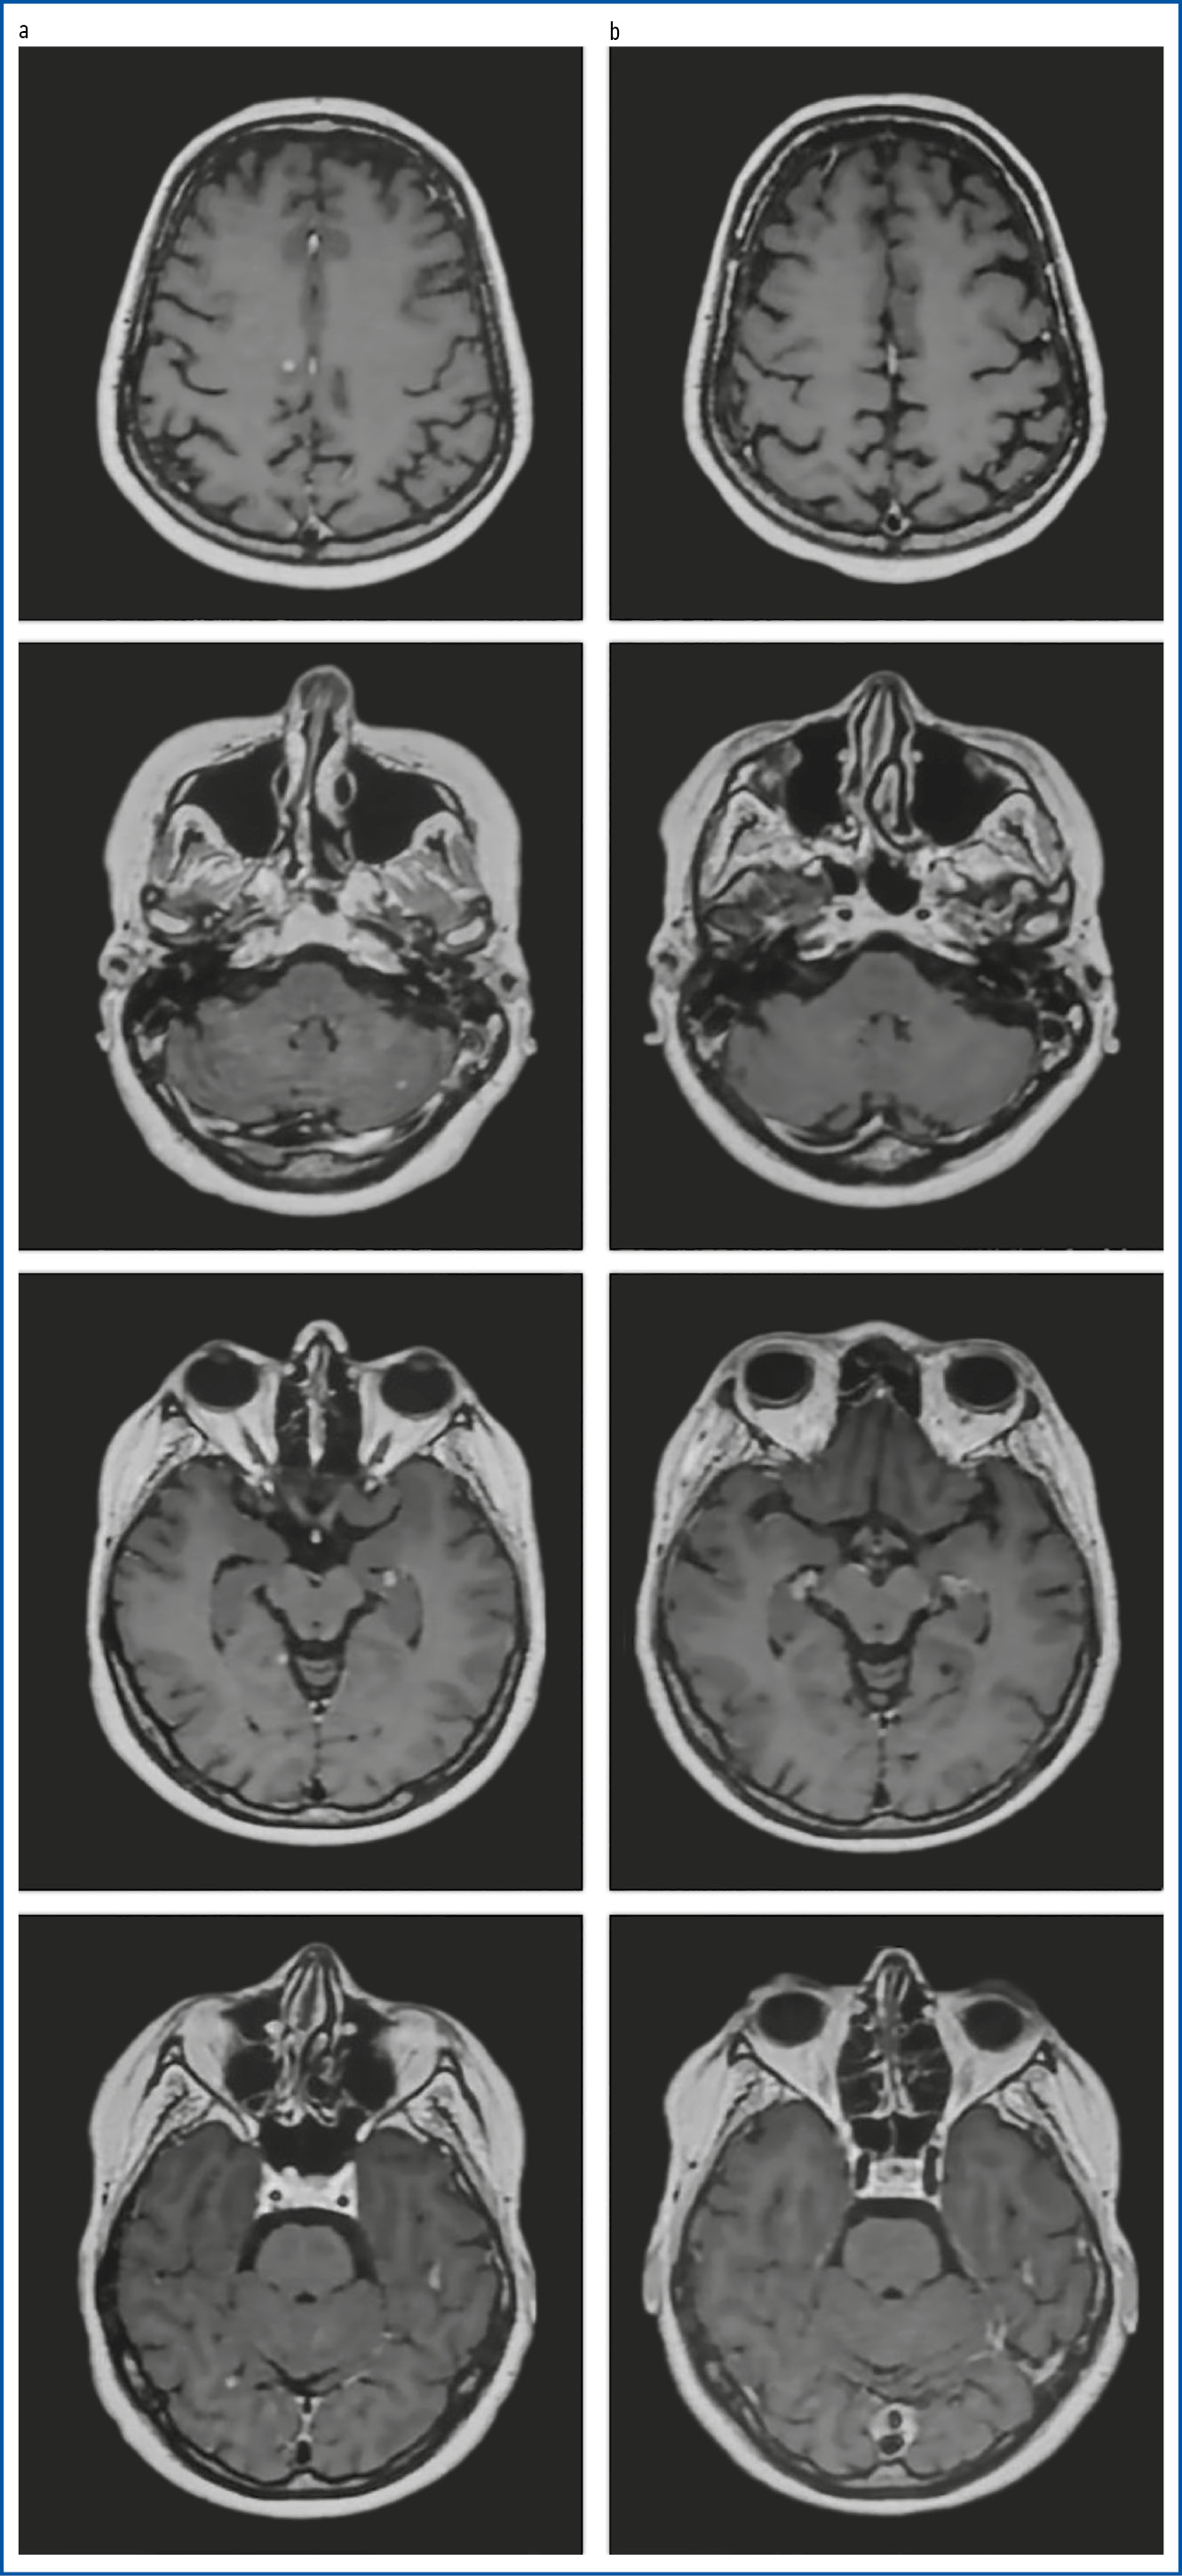

По данным контрольной МРТ ГМ от 23 января 2024 г. выявлены новые МГМ (рис. 1, a).

Рис. 1. МРТ ГМ в динамике: a − данные от 23.01.2024; b − данные от 19.02.2025.

Fig. 1. Serial brain MRI: a − dated 23.01.2024; b − dated 19.02.2025.

11 марта 2024 г. пациентке выполнен контроль МРТ ГМ после 3 курсов препаратом трастузумаб дерукстекан. Выявлены признаки регресса очагов метастатического характера в гемисферах ГМ и мозжечке. По сравнению с исследованием от 24 января 2024 г. динамика положительная.

С 30 января 2024 г. по настоящее время пациентке проводят паллиативную ТТ препаратом трастузумаб дерукстекан. Всего выполнено 20 курсов. Эффект терапии: полный ответ после 6 курсов лечения. Данные МРТ в динамике приведены на рис. 1.